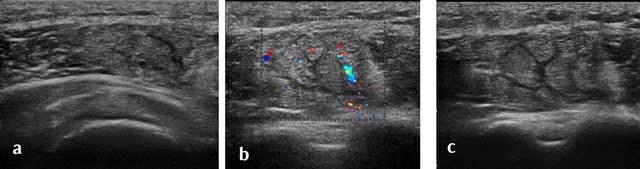

Figure 8

Axial posterior view of the humerus. delt: Deltoid muscle, hum: humerus, art circ post: Axillar artery.

Posterior axial section allows identifying the circumflex artery in an axial plane. Color Doppler can be useful to confirm the vascular origin (Figure 7 and Figure 8).